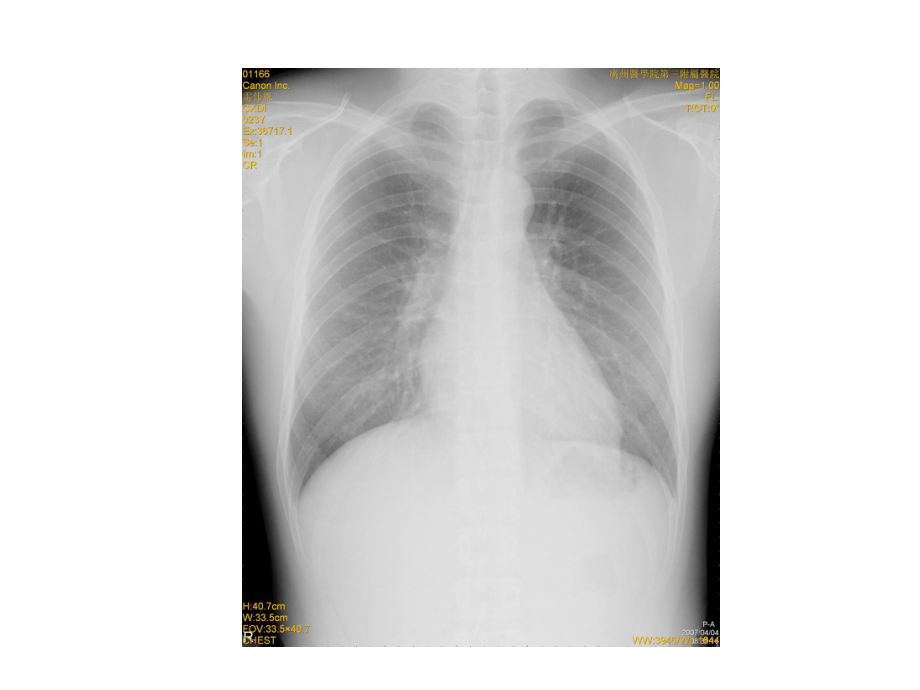

1、急腹症及腹膜腔疾病的影像学诊断 腹部是指膈肌以下、盆腔以上的解剖部位。包括腹部脏器(以消化、泌尿、生殖等系统为主)、腹膜腔、腹膜后间隙及腹壁。 急腹症急急 腹腹 症症 国内仍以腹部x线和B超作为首选的检查方法,必要时再做CT检查1.1.1 X线腹平片: 至少要求站立位、仰卧前后位;其它如侧位仰卧水平侧位、侧卧水平正位、倒正、侧位;1.1.2 透视: 除可以观察病变外,还可动态观察膈肌运动和胃肠蠕动。1.检查技术腹部平片(abdominal plain film)l优势(merits): 显示腹腔内游离气体、腹水、肠腔内胀气或积液、 肠曲固定、腹内高密度影等;l适应症(indications):

2、 消化道穿孔、肠梗阻、泌尿系阳性结石、腹腔内高密度异物或钙化等。正常腹平片站立前后位平片侧卧水平正位平片1.2 造影检查1.2.1 钡剂、空气灌肠:肠套叠、乙状结肠扭转、结肠癌;1.2.2 钡餐:先天性幽门梗阻、十二指肠梗阻;1.2.3 泛影葡胺:上消化道出血、穿孔及肠梗阻;1.2.4 选择性或超选择性血管造影:急性消化道大出血。1.3 CT检查 平扫/+增强扫描CT (computed tomography)CT (computed tomography)l优势 (merits):较全面、准确发现病变,显示病变的程度和范围 (lesion detection);显示腹内较早期、微小的病变;合

3、理使用窗技术,有利于显示腹腔内少量游离气体;在大多数情况下,还能判断病变的性质 (lesion characterization)。2. 正常影像学表现正常影像学表现 2.1 X线平片线平片 腹壁与盆壁腹壁与盆壁 腹膜后、肾周脂肪呈灰黑影,胁腹线腹膜后、肾周脂肪呈灰黑影,胁腹线 腰大肌、腰方肌、闭孔肌、提肛肌、腰大肌、腰方肌、闭孔肌、提肛肌、 骨性结构骨性结构 实质器官实质器官 肝、脾、胰、肾、子宫肝、脾、胰、肾、子宫 空腔器官空腔器官 胃肠道、胆囊、膀胱胃肠道、胆囊、膀胱 ( ) 胁腹线( ) 肾周脂肪线( ) 肝角( ) 腰大肌2.2 正常大、小肠的宽度 空肠内径:1.5-2.5cm 回肠

4、内径:1.0-2.0cm 盲肠内径:5.0-6.0cm 左半结肠:3.0-4.0cm3. 基本病变3.1 腹腔内积气 : 游离、局限性 ; 气腹的影像表现l站立位投照:膈下透明的新月形气体影;l侧卧水平位投照:气体浮游至靠上方侧腹壁与腹内脏器外侧壁之间;l仰卧前后位投照:气体聚集于腹腔前分,可使肝镰状韧带和脏器外侧壁显示;lCT表现:游离气体大多聚集于腹腔前份。( )腹腔积气( )腹腔积气)腹腔积气肠穿孔大量游离气体,气液腹肝脏镰状韧带3.2 空腔器官积气、积液并管腔扩大,形成液气平面征;3.3 腹内肿块影;3.4 腹内高密度影;3.5 下胸部异常。空腔器官积气、回肠起始段积液并管腔扩大空腔器